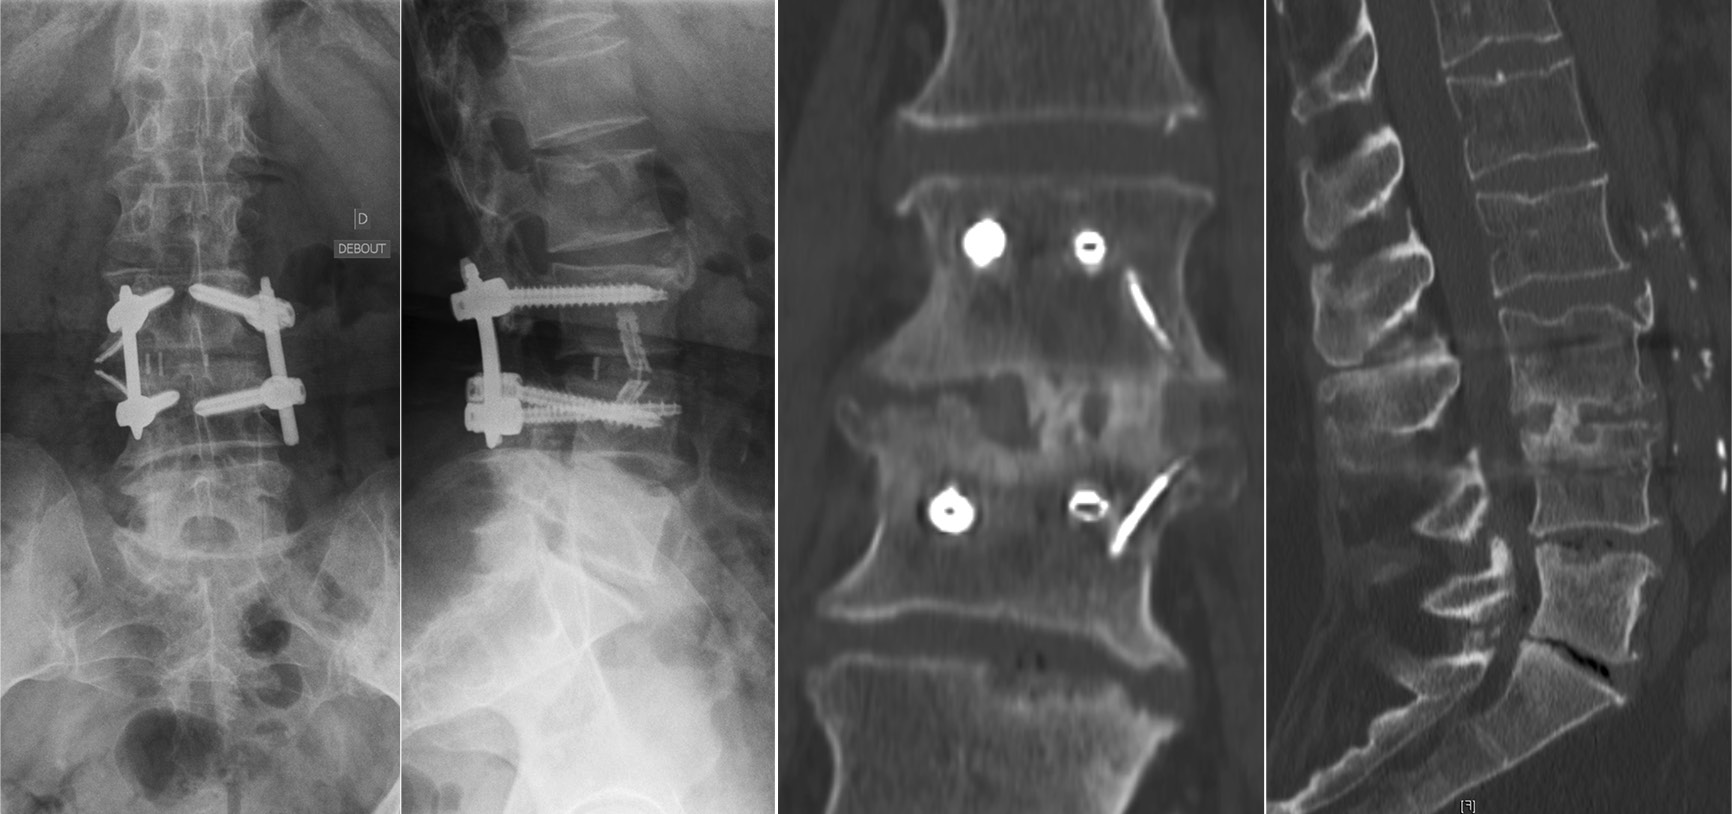

腰椎L3-4椎间融合联合后路经皮椎弓根钉内固定。1年随访时CT显示椎间骨性融合

如果术后患者在随访过程中出现疼痛,并且X光片显示内固定棒断裂,则应高度怀疑脊柱出现不愈合的情况。在判断节段不融合时,应不断强调内固定棒在单一节段上发生断裂,并不代表仅存在该节段的脊柱不融合,应警惕多节段不融合的风险。所有脊柱节段均应在影像学上进行仔细检查,并在术中进行探查,以避免多次的翻修手术。文中,作者还特别强调了Ponte截骨在应用此类患者时的注意事项。Ponte截骨术在当通过有力的加压对节段性后凸畸形进行矫正时,前方骨赘可能会出现破裂,导致前方狭窄的椎间隙张开。此时,必须通过前路支撑与植骨来稳定这些节段,以防止术后矫正丢失与不融合情况的发生。如果已经发生,则建议使用OLIF进行前路的支撑融合。

Ponte截骨使狭窄的间隙在前方张开,后期可能缺乏良好的前柱支撑出现不融合

作者在文中描述避免不融合与内固定棒断裂的方法时说明,如果固定节段包括骶骨与骨盆时,仅仅依赖后方的融合而没有前柱的支撑可能还是不够的。作者仍然建议在前柱采用ALIF或TLIF技术避免不融合或再手术的发生。同时,今年来在针对内固定棒断裂的问题时,双棒技术的应用已表现出良好的临床结果,在文献报道中能够降低不愈合的风险。增加卫星棒的目的在于增加两个额外的内固定棒来加强固定并分担一部分应力,降低单一内固定棒所承受的应力。